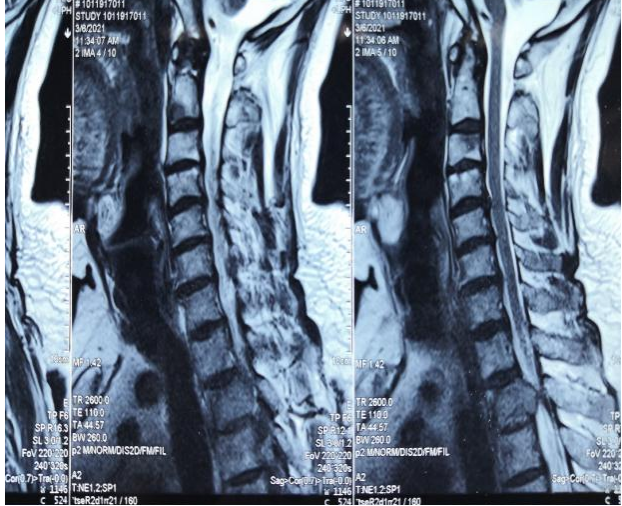

颈椎磁共振检查结果让王爷爷和家人大吃一惊。

心脏后面,胸椎第二节椎骨上长了个瘤子,瘤子很大,占椎管的 90%,已经压迫脊髓和神经。

经过多方打听,儿女带着他找到郑州大学附属郑州中心医院。神经脊柱外科主任孙国绍查阅王爷爷病历资料,询问病史并进行详细的体格检查,最终确诊为肾癌胸 2 椎体转移病变组织突向后方椎管导致脊髓受压。